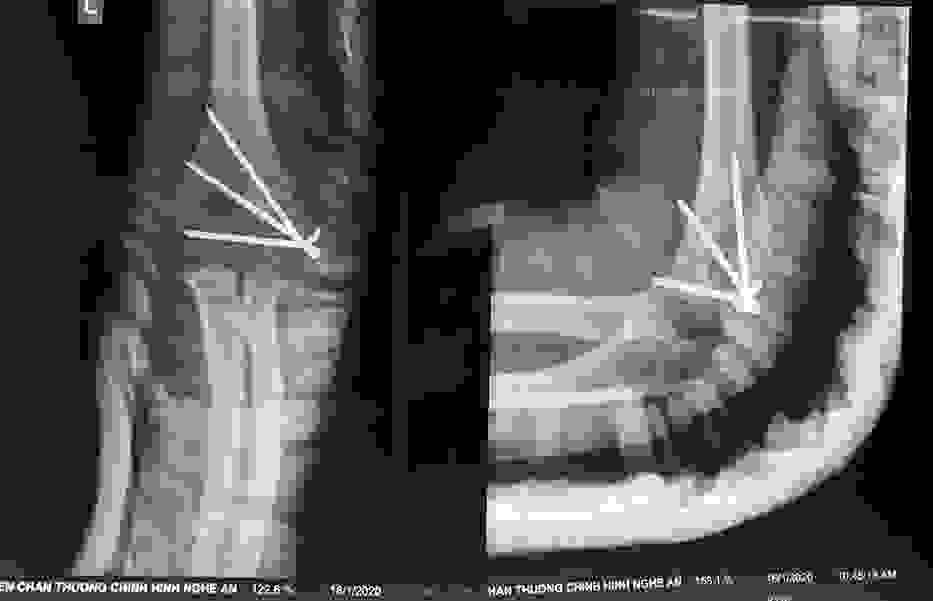

Phẫu thuật thành công ca bệnh hiếm gặp...khớp giả bẩm sinh xương chày

26/06/2019 17:00

Đã xem: 3441

Bệnh viện Chấn thương- Chỉnh hình Nghệ An, vừa phẫu thuật thành công cho bệnh nhi khớp giả bẩm sinh xương chày